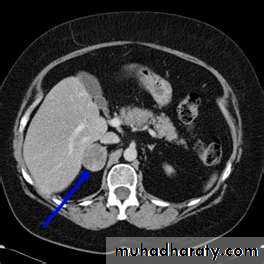

2- imaging study for the localization of the phaeochromocytoma and/or metastases. MRI is preferred because contrast media used for CT scans can provoke paroxysms.

CT/MRI of the chest and abdomen, a bone scan.

3-MRI and CT are equally effective in distinguishing adrenocortical adenoma from carcinoma .